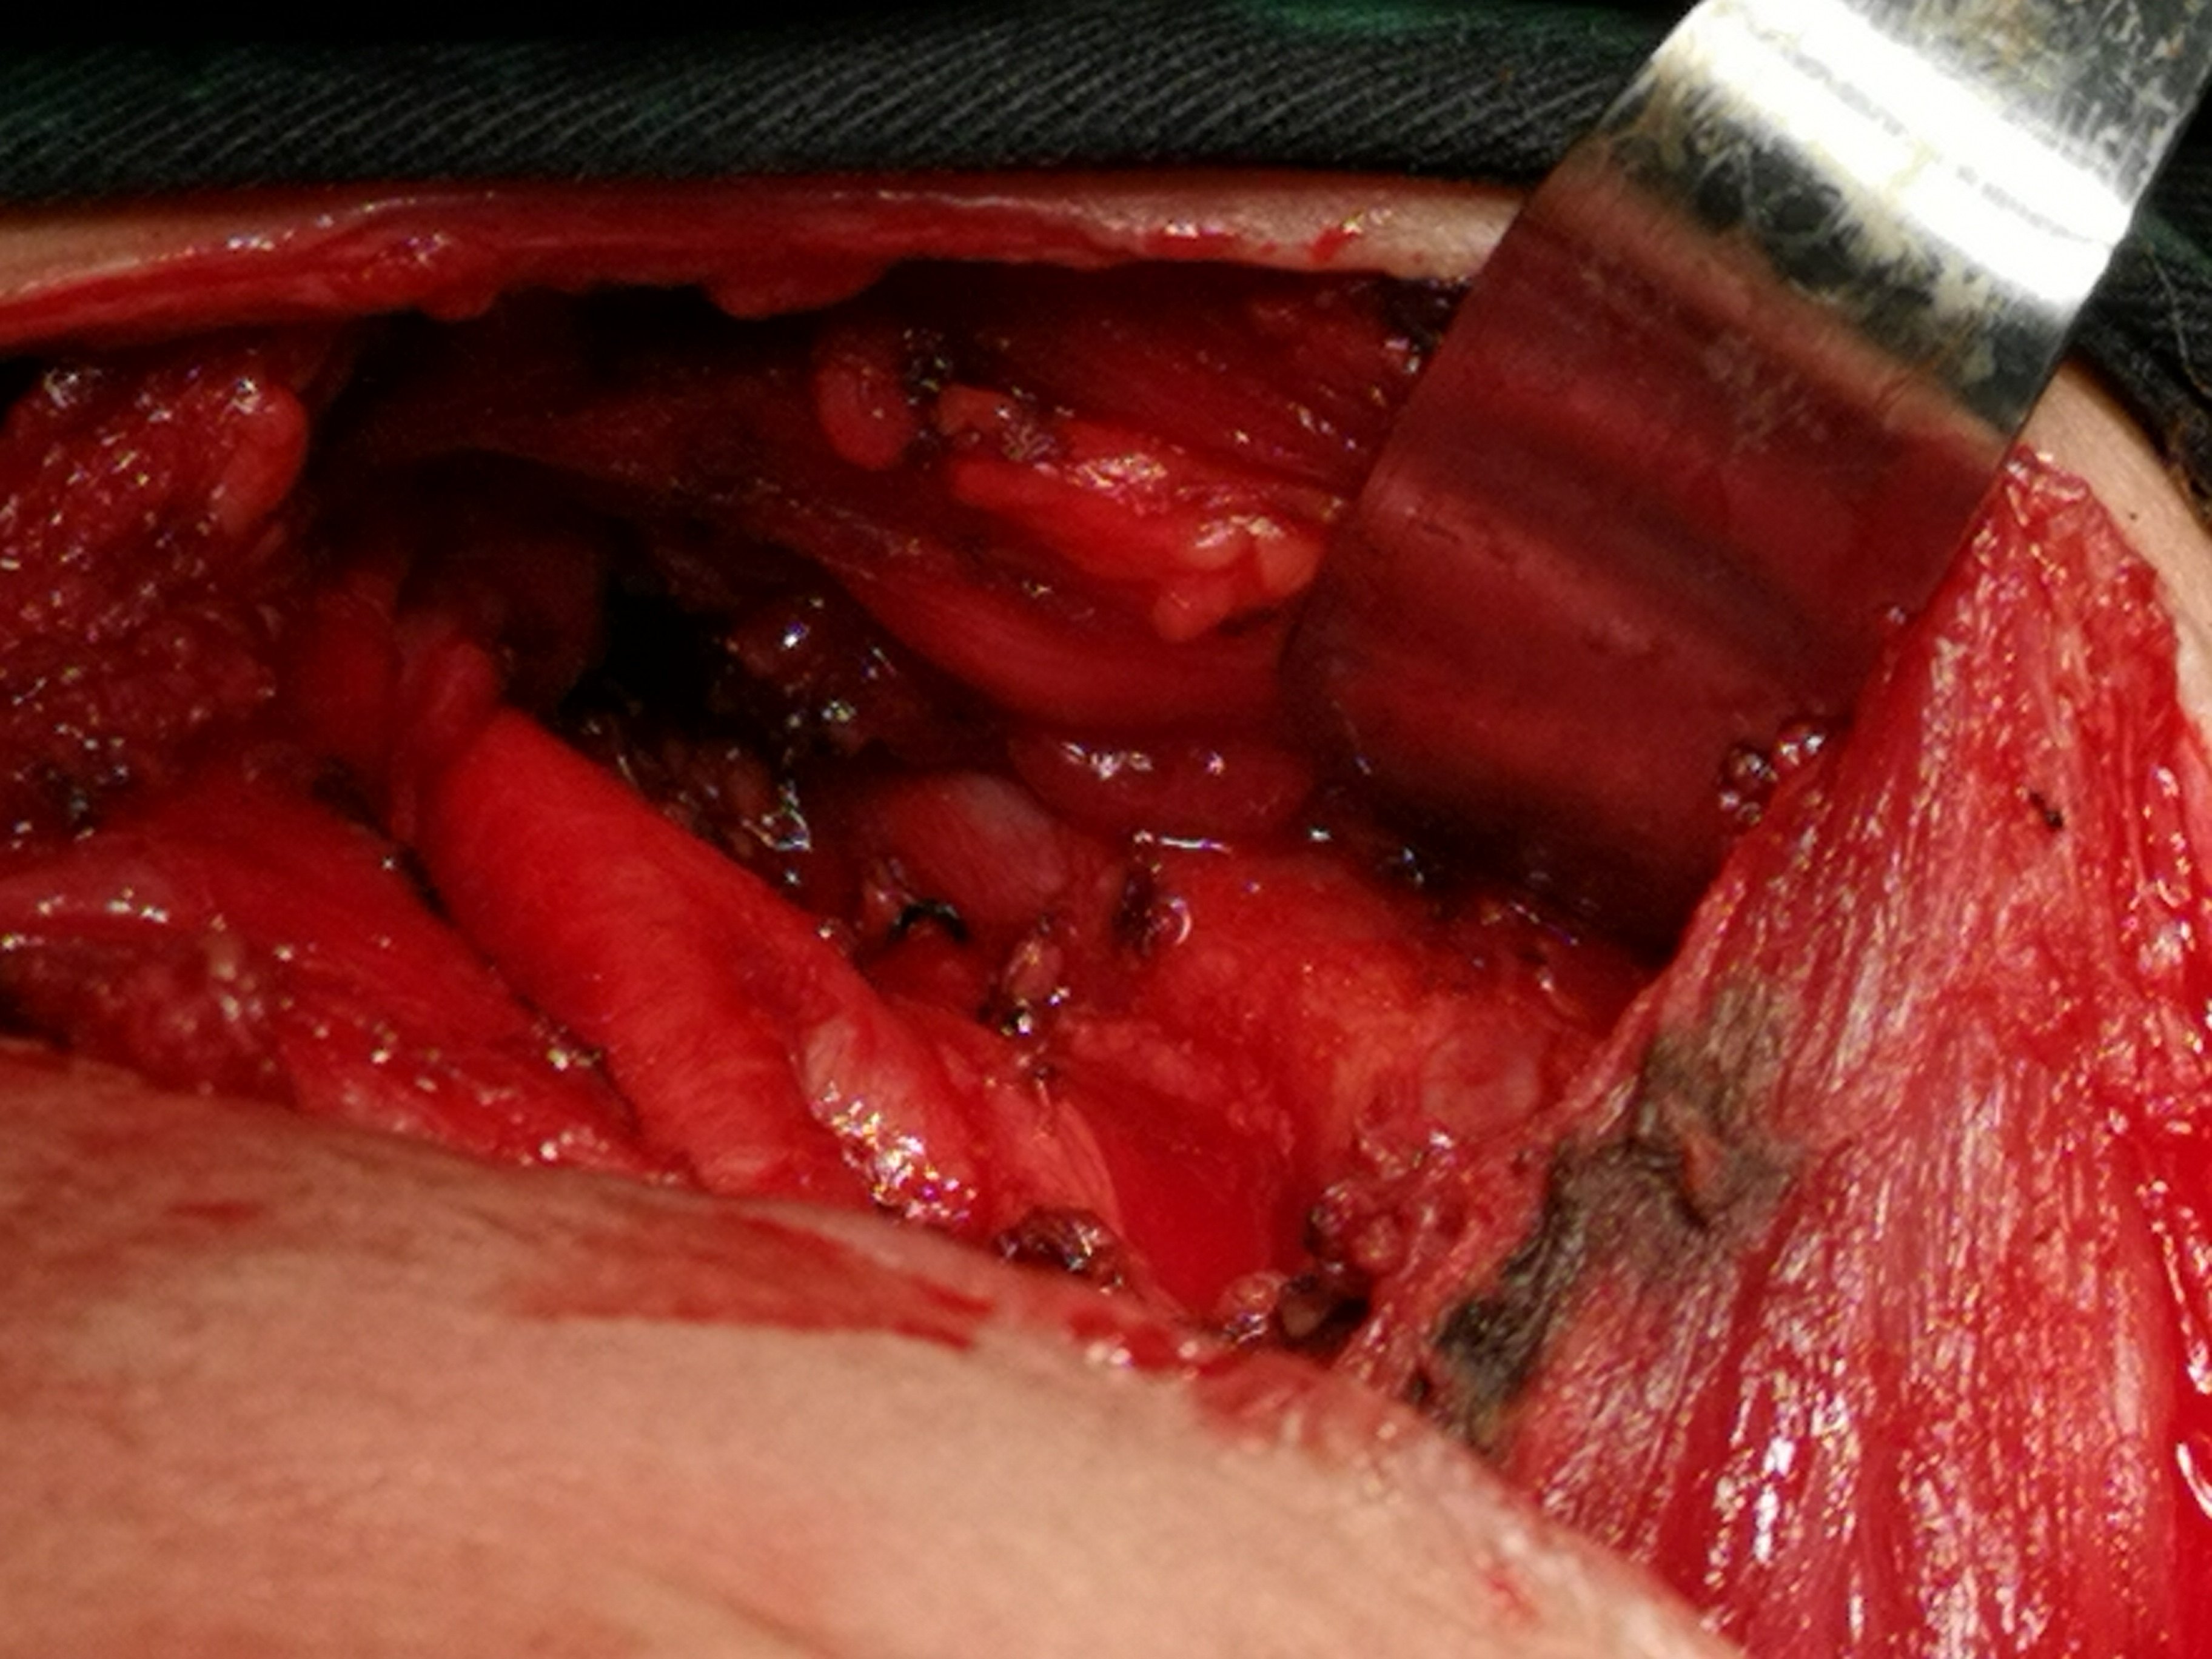

甲状腺癌再次手术

病例2 右2,右4R区,左6区残留,颈部切口清扫,未开胸